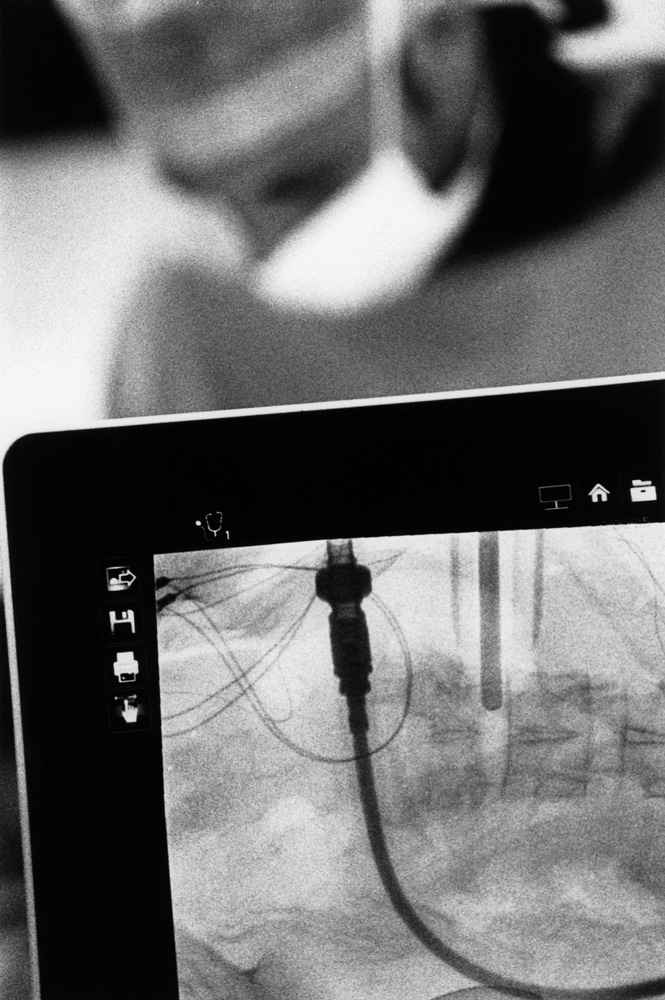

Da metà giugno a fine novembre 2021, Renato D’Agostin e la sua macchina fotografica hanno avuto accesso esclusivo alla clinica: dal centro di riabilitazione alle sale operatorie, dai reparti di degenza all’area amministrativa, dal laboratorio di analisi agli ambulatori.

Il risultato di questo viaggio immersivo nel mondo e negli spazi della struttura sono oggi 20 scatti unici e irripetibili, raccolti in questo catalogo e nella mostra “La Cura.

La clinica Rizzola nelle fotografie di Renato D’Agostin” ospitata presso Spazio Mostre Italvanto Battistella, a San Donà di Piave, dal 7 al 17 gennaio 2022 Gli scatti trovano oggi esposizione permanente all’interno della Casa di Cura Sileno e Anna Rizzola.